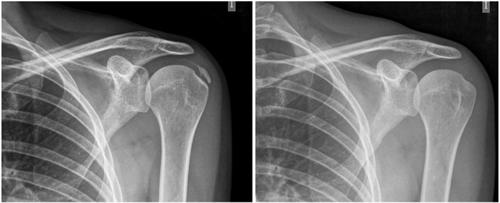

Calcific tendinitis of the shoulder: risk factors and effectiveness of iontophoresis with acetic acid 5 % plus ultrasound: prospective quasi-experimental study at 5 years with 138 cases

Figure 1